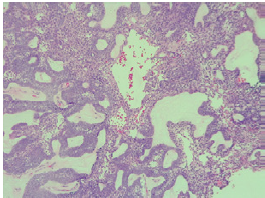

Eleven years after the initial surgery, and after 3 surgeries, a new local relapse was discovered. On physical examination, the patient was found in good condition, with left facial palsy and mass in left masticator space with extension to hard and soft palate, in addition to left submandibular ganglion conglomerate. Contrasted CT showed a mass that involved the left masticator space, lobed, of heterogeneous density with extension towards the skull and average cranial fossa of 36.7x53.6x42mm in anteroposterior section (Figures 3 and 4); biopsy and histopathological study confirmed ameloblastoma.

Computed tomography of paranasal sinuses showing heterogeneous mass in left masticator space with extension to the base of the skull and middle cranial fossa.

Figure 4: Computed tomography of paranasal sinuses showing heterogeneous mass in left masticator space with extension to the base of the skull and middle cranial fossa.

Source: Document obtained during the study.